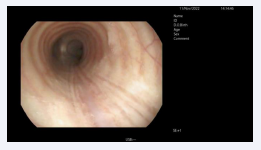

On I day of hospitalization, in multidisciplinary agreement and after the acquisition of informed consent, she underwent a first bronchoscopy under deep sedation which revealed in trachea, at about 7.5 cm from the chordal plane, a laceration of the pars membranacea extended for 5 cm [Figure 3], and within a rupture extending longitudinally for about 3 cm.

Longitudinal pars membranacea rupture of the trachea.

Figure 3: Longitudinal pars membranacea rupture of the trachea.